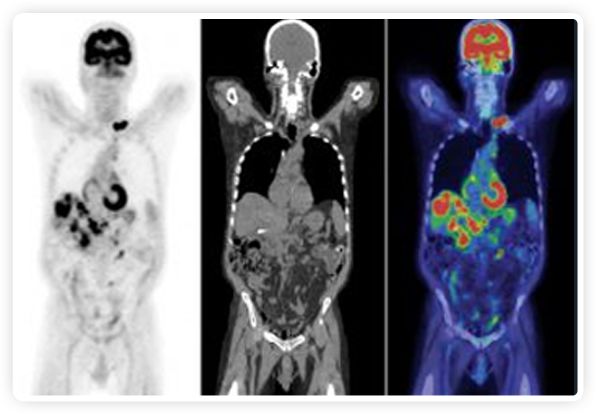

提起放療設(shè)備的引導(dǎo)系統(tǒng),大家通常會(huì)想到結(jié)構(gòu)性成像的CT或核磁。但你有沒有想過用功能性成像來引導(dǎo)放療呢?美國的一家醫(yī)療器械公司從2011年就致力于研究開發(fā)用PET提供生物學(xué)指導(dǎo)放射治療的設(shè)備BgRT。BgRT能實(shí)時(shí)利用癌癥的生物學(xué)特征作為信號指導(dǎo)治療全身腫瘤。

正電子發(fā)射斷層掃描(PET)是癌癥檢測中已建立的成像標(biāo)準(zhǔn),與其他成像方式相比,PET能提供高靈敏度和特異性的圖像。

到目前為止,放射腫瘤學(xué)中(使用的圖像主要是結(jié)構(gòu)性的,而PET圖像可以提供生物學(xué)信息。通過使用注射示蹤劑,例如18-FDG,PET可以描繪腫瘤的代謝活性,使其“點(diǎn)亮”。(FDG是用于可視化癌癥代謝的最廣泛使用的示蹤劑。與正常組織相比,腫瘤細(xì)胞保留更高水平的FDG。)不同的PET示蹤劑可以識別腫瘤的不同生物學(xué)特征,例如特定生物標(biāo)志物抗原(例如,PSMA)或甚至探測免疫系統(tǒng)本身(例如,PDL1表達(dá)或活化的T細(xì)胞)。

RefleXion將PET成像與立體定向放射治療相結(jié)合。在注射示蹤劑后,RefleXion的技術(shù)基于示蹤劑信號實(shí)時(shí)地在一個(gè)或多個(gè)目標(biāo)上引導(dǎo)治療性X射線。使用這種專有方法,RefleXion的平臺有可能比現(xiàn)有系統(tǒng)向癌癥病變提供更高劑量的輻射,并改善周圍健康組織的保護(hù)。